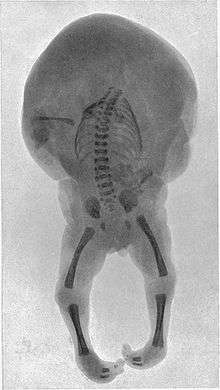

Acardiac twin

The acardiac twin is a parasitic twin that fails to properly develop a heart, and therefore generally does not develop the upper structures of the body. The parasitic twin, little more than a torso with or without legs, receives its blood supply from the host twin by means of an umbilical cord-like structure (which often only has 2 blood vessels, instead of 3), much like a fetus in fetu, except the acardiac twin is outside the host twin's body. Although the reason is not fully understood, it is apparent that deoxygenated blood from the pump twin is perfused to the acardiac twin. The acardiac twin grows along with the pump twin, but due to inadequate oxygenation it is unable to develop the structures necessary for life, and presents with dramatic deformities.

Although no two acardiac twins are alike, twins with this disorder are grouped into 4 classes: Acephalus, anceps, acormus, and amorphus.

- Acephalus - The most common type, lacking a head, though it may have arms. Thoracic organs are generally absent, and disorganized & unidentifiable tissues take their place.

- Anceps - The acardius has most body parts, including a head with face and incomplete brain. Organs, though present, are crudely formed.

- Acormus - This type has no apparent body and the umbilical cord is seemingly attached to the neck, but x-rays or dissection reveal thoracic structures in the apparent head. One had a leg apparently attached to the head. This may be due to embryopathy degenerating a once normal embryo.

- Amorphus - This extreme form not only lacks a head and limbs, but also any internal organs, and consists of tissues with blood vessels branching from the umbilical cord. Some may only be stem cell tumors.[2]

The acardiac twin may also be described as a hemiacardius, which has an incompletely formed heart, or a holoacardius, in which the heart is not present at all.[6]